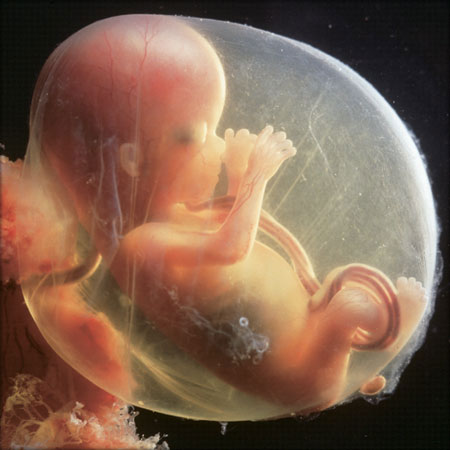

Развој бебе у стомаку мајке

од зачећа 12 недеља